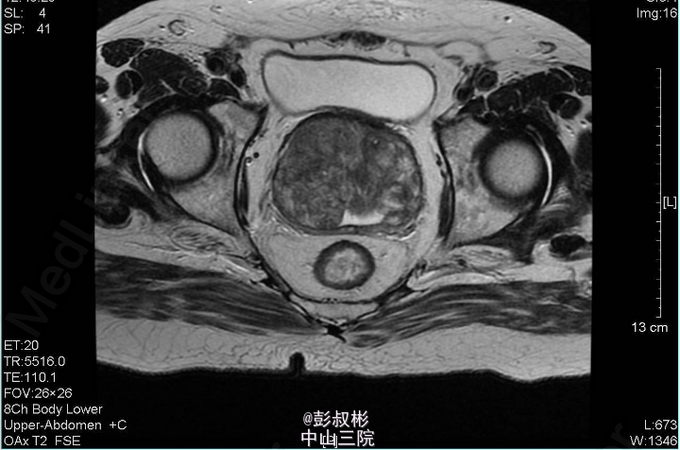

4、查体:直肠指检:前列腺明显增大,大小约:7×6cm,质韧,中央沟消失,可触及一3*2cm结节,质硬,无压痛,界清,指套未见染血 5、辅助检查:外院查尿常规示:红细胞31022个/ul,CA19-9:60.9U/ml,F-PSA:6.45ng/ml,T-PSA:21.2ng/ml,彩超示:膀胱区及前列腺内低回声团,盆腔CT示:膀胱癌并前列腺转移。我院血常规:血红蛋白浓度119.000g/L,白细胞总数7.340x10E9/L。 尿常规:潜血+++,红细胞计数12050.20个/ul,白细胞计数49.50个/ul。 生化全套:肌酐(酶法)218.800umol/L,尿酸658umol/L,血淀粉酶227U/L,谷丙转氨酶64 U/L,谷草转氨酶49U/L,谷氨酰转肽酶340U/L。 PSA两项:总前列腺特异性抗原22.362ng/ml,游离前列腺特异性抗原5.957ng/ml。 盆腔MR:1、考虑前列腺癌并出血,膀胱后壁、双侧精囊腺受压。2、右侧耻骨联合小结节,考虑转移瘤可能性大;左侧坐骨结节所见,未除外转移瘤可能。3、考虑右侧股骨头坏死。胸片示:主动脉硬化,心电图正常。 肺功能:通气功能大至正常。 心脏彩超:EF 65%。主动脉瓣钙化并反流(轻度)。左室收缩功能正常。左室舒张功能减退。 动态心电图:1、窦性心率。2、稀发房早。3、肢体导联低电压 肝胆胰脾彩超:胰头稍大,慢性胆囊炎声像,胆囊多发结石,轻度脂肪肝。 前列腺穿刺:结果未出 骨扫描:全身未见骨转移瘤